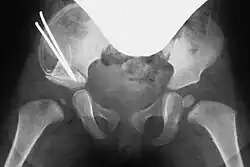

Post-Pemberton osteotomy on the right, with the bone wedge fixed by two Kirschner wires

In both techniques, a suitably shaped bone wedge is inserted into the resulting gap under X-ray guidance. If needed, the wedge can be fixed with an osteosynthesis wire (Kirschner wire). The procedure typically takes 45 to 60 minutes for an experienced surgeon.[3][11]